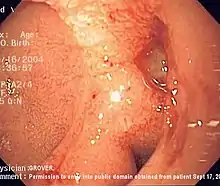

Endoscopic image of a posterior wall duodenal ulcer with a clean base, which is a common cause of upper GI hemorrhage.